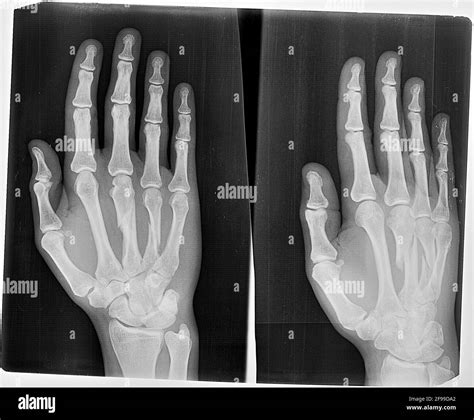

A broken hand, often diagnosed through an X-ray, involves a fracture in one or more of the bones in the hand. The hand is composed of 27 bones, including the metacarpals, phalanges, and carpals. Each of these bones can be susceptible to fractures, which can range from minor cracks to severe breaks.

• X-rays: X-rays are the primary imaging tool used to confirm the presence and type of fracture. They provide detailed images of the bones and can help determine the severity of the injury.